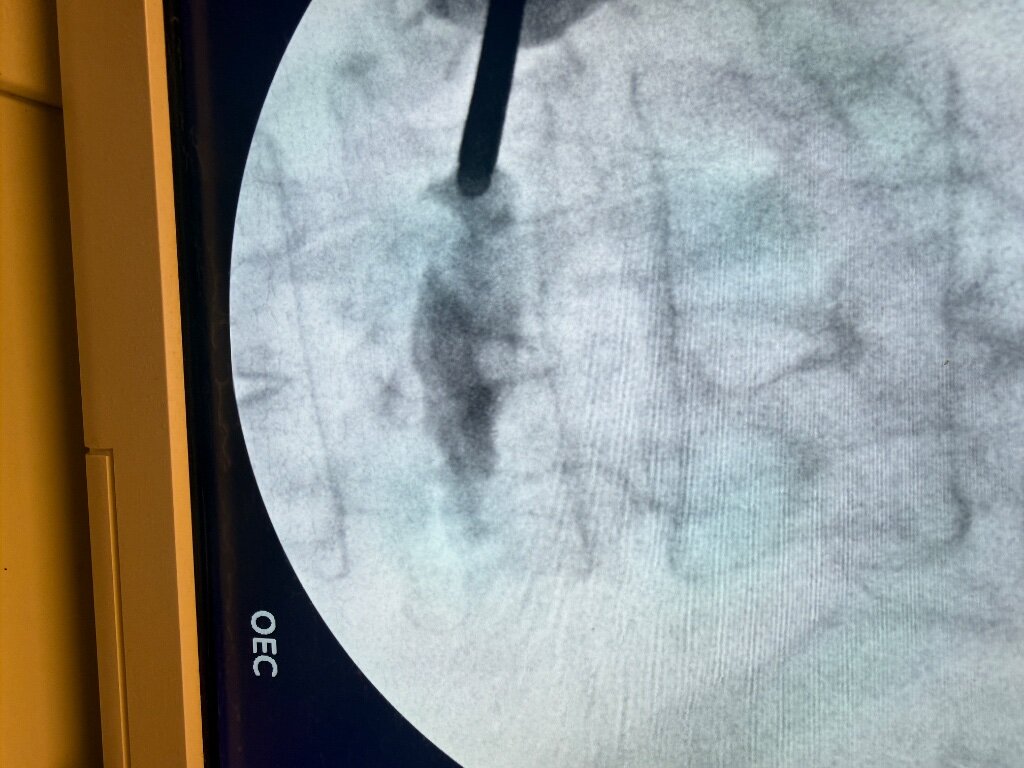

This is my case from today. 85 years old, injury seven weeks out, getting progressively worse. Pain 9-10/10, unable to independently transfer or ambulate, on opiods. Been to ER twice, admitted once for pain control, then snf. Referred to me by pcp earlier in week, did add on case. Walked out pain free. I see this outcome routinely, not always 100%, but at least 60-80% within a day or two.

Attachments

• IMG_8488.jpeg

IMG_8488.jpeg

279.6 KB · Views: 75

• IMG_8482.jpeg

IMG_8482.jpeg

110.7 KB · Views: 69

• IMG_8483.jpeg

IMG_8483.jpeg

192.2 KB · Views: 74

• IMG_8481.jpeg

IMG_8481.jpeg

119 KB · Views: 69